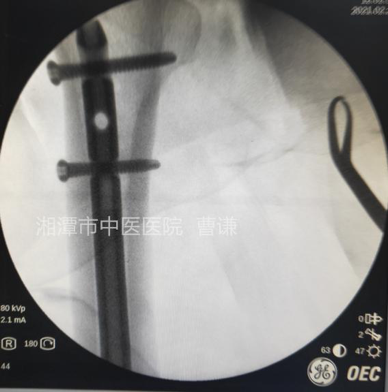

钢丝主要用于复位,固定完成后一般可以取出,直接用老虎钳提起拧断抽出即可。

此例第一捆钢丝由于拧断时从结头中段断裂了,所以干脆留置了。

透视侧位骨折对位对线良好,锁钉位置良好。